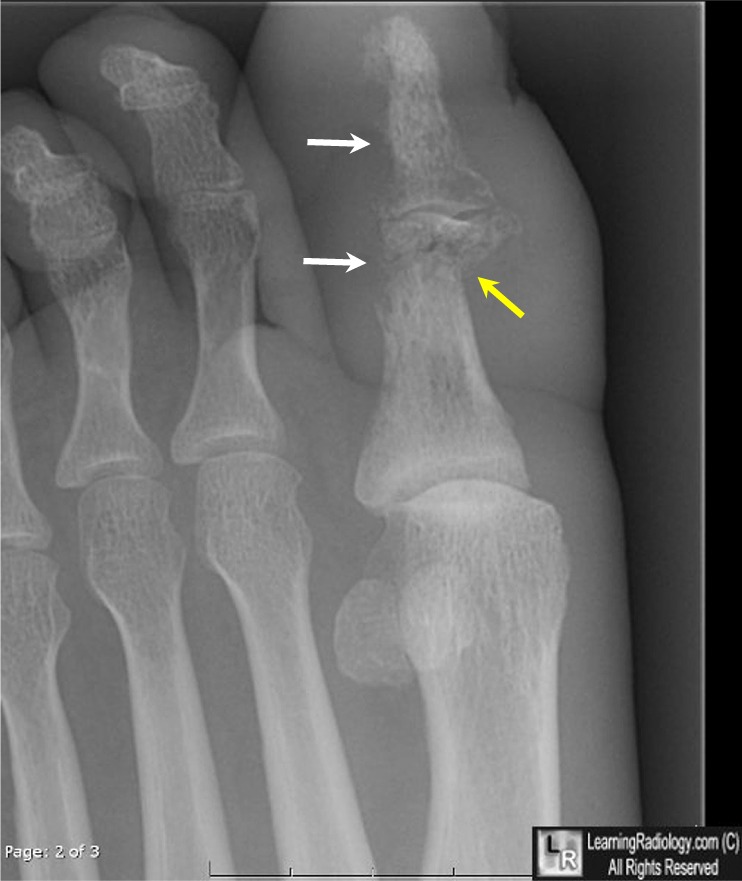

Periosteal reaction. Periosteal reaction on a healing supracondylar fracture. Specialty. Orthopedics. A periosteal reaction is the formation of new bone in response to injury or other stimuli of the periosteum surrounding the bone. It is most often identified on X-ray films of the bones.

Periosteal reaction. Jump to navigation Jump to search. A periosteal reaction is the formation of new bone in response to injury or other stimuli of the periosteum surrounding the bone.

Periosteal reaction is a nonspecific radiographic finding that indicates new bone formation in reaction to the abnormal stimulants. Periosteal reactions may be broadly characterized as benign or aggressive, or more specifically categorized by pattern.

Periosteal reaction results when cortical bone reacts to one of many possible insults. Tumor, infection, trauma, certain drugs, and some arthritic conditions can elevate the periosteum from the cortex and form various patterns of periosteal reaction (Fig.

Periosteal reaction, also known as periostitis or periosteitis, is a nonspecific radiographic finding that indicates periosteal irritation. Periosteal reactions may be broadly characterized as benign or aggressive, or more specifically categorized by pattern.

Orthopedics. A periosteal reaction is the formation of new bone in response to injury or other stimuli of the periosteum surrounding the bone. It is most often identified on X-ray films of the bones.

A periosteal reaction can result from a large number of causes, including injury and chronic irritation due to a medical condition such as hypertrophic osteopathy, bone healing in response to fracture, chronic stress injuries, subperiosteal hematomas, osteomyelitis, and cancer of the bone. It may also occur as part ...

The periosteum may react to irritation by the production of new bone. The type of periosteal reaction is often indicative of the severity of the lesion provoking it. In its earliest form it appears as a fine irregular reaction giving the bone a blurred or indistinct margin at the site of the lesion.

A thin periosteal reaction might represent an early stage of a highly aggressive bone lesion or a chronic, benign process ( Fig. 3. 1 ). On the other hand, a thick periosteal reaction usually suggests a benign condition.

Periosteal reaction may also be grouped into several patterns: smooth, solid or thick, and aggressive (laminar, sunburst, Codman triangle, and cloaking). Smooth periosteal reaction consists of one or multiple unbroken layers of ossified periosteum along the cortical surface.

Periosteal Reaction. The periosteum is a membrane that covers the majority of bone except at locations at and near cartilage. How periosteum responds to stimuli (e.g., trauma, infection, metabolic process, and neoplasm) can often give clues to the etiology of the underlying stimulus. An aggressive or destructive process will often greatly alter ...

An aggressive or destructive process will often greatly alter the periosteum, whereas a nonaggressive process usually gives the periosteum the opportunity to remodel with a more orderly architecture. The distribution of periosteal reaction (focal or diffuse) may give clues to the underlying process.